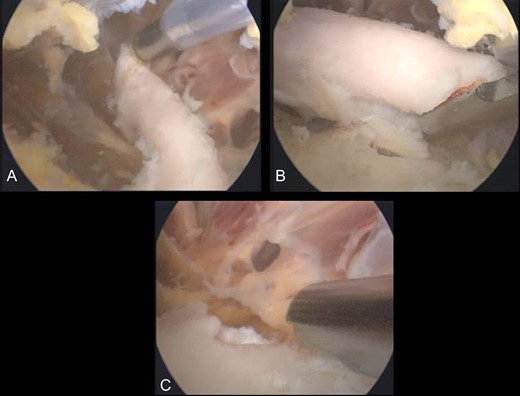

The second case involved an 18 years old male with pain and swelling at the anterior surface of the left knee, under the rectus femoris muscle over the patella. Symptoms exacerbated during knee bending over 90 degrees. X-rays and MRI revealed an extra-articular exostosis, just over the suprapatellar pouch (Figs. 3A and B). Under general anesthesia, a standard antero-lateral portal was used to access the knee arthroscopically. The capsule of the suprapatellar pouch was divided providing access to the adjacent extra-articular osteochondroma. Through a medial, a far supero-medial and supero-lateral portal, the exostosis resected by using an osteotome and removed with a grasper through the supero-lateral portal. The lesion had maximum dimensions 3.1 × 1.4 cm and its histopathological examination set the diagnosis of osteochondroma. Postoperatively, the patient was pain free with full range of knee motion. No recurrence was observed at 9 months (Fig. 4).